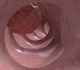

Screening is carried out by taking a small stool sample and testing it for the presence of blood. This is called the faecal occult blood test or FBT. An extra screening test is being introduced over the next three years for all people at age 55. This test involves flexible sigmoidoscopy which involves looking for polyps and growths within the intestines with a flexible tube with a camera at its tip.